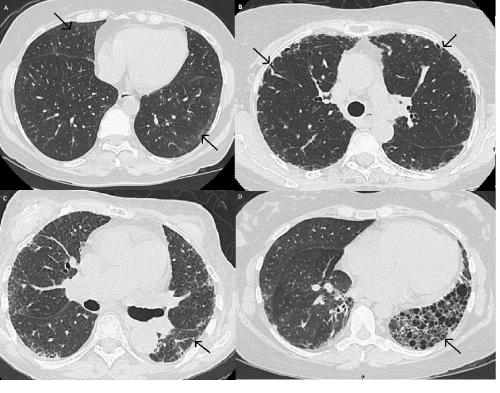

| Figure 1: Typical HRCT abnormalities in SSc-ILD. A. Pure ground glass opacities can be seen peripherally, predominantly in the right middle and left lower lobes; B. Subpleural thickened reticular markings are associated with traction bronchiectasis and bronchiolectasis; C. Ground glass opacities are mixed with fine reticular septal thickening diffusely; D. Extensive macrocystic honeycombing has replaced most of the left lower lobe and is associated with significant volume loss. |